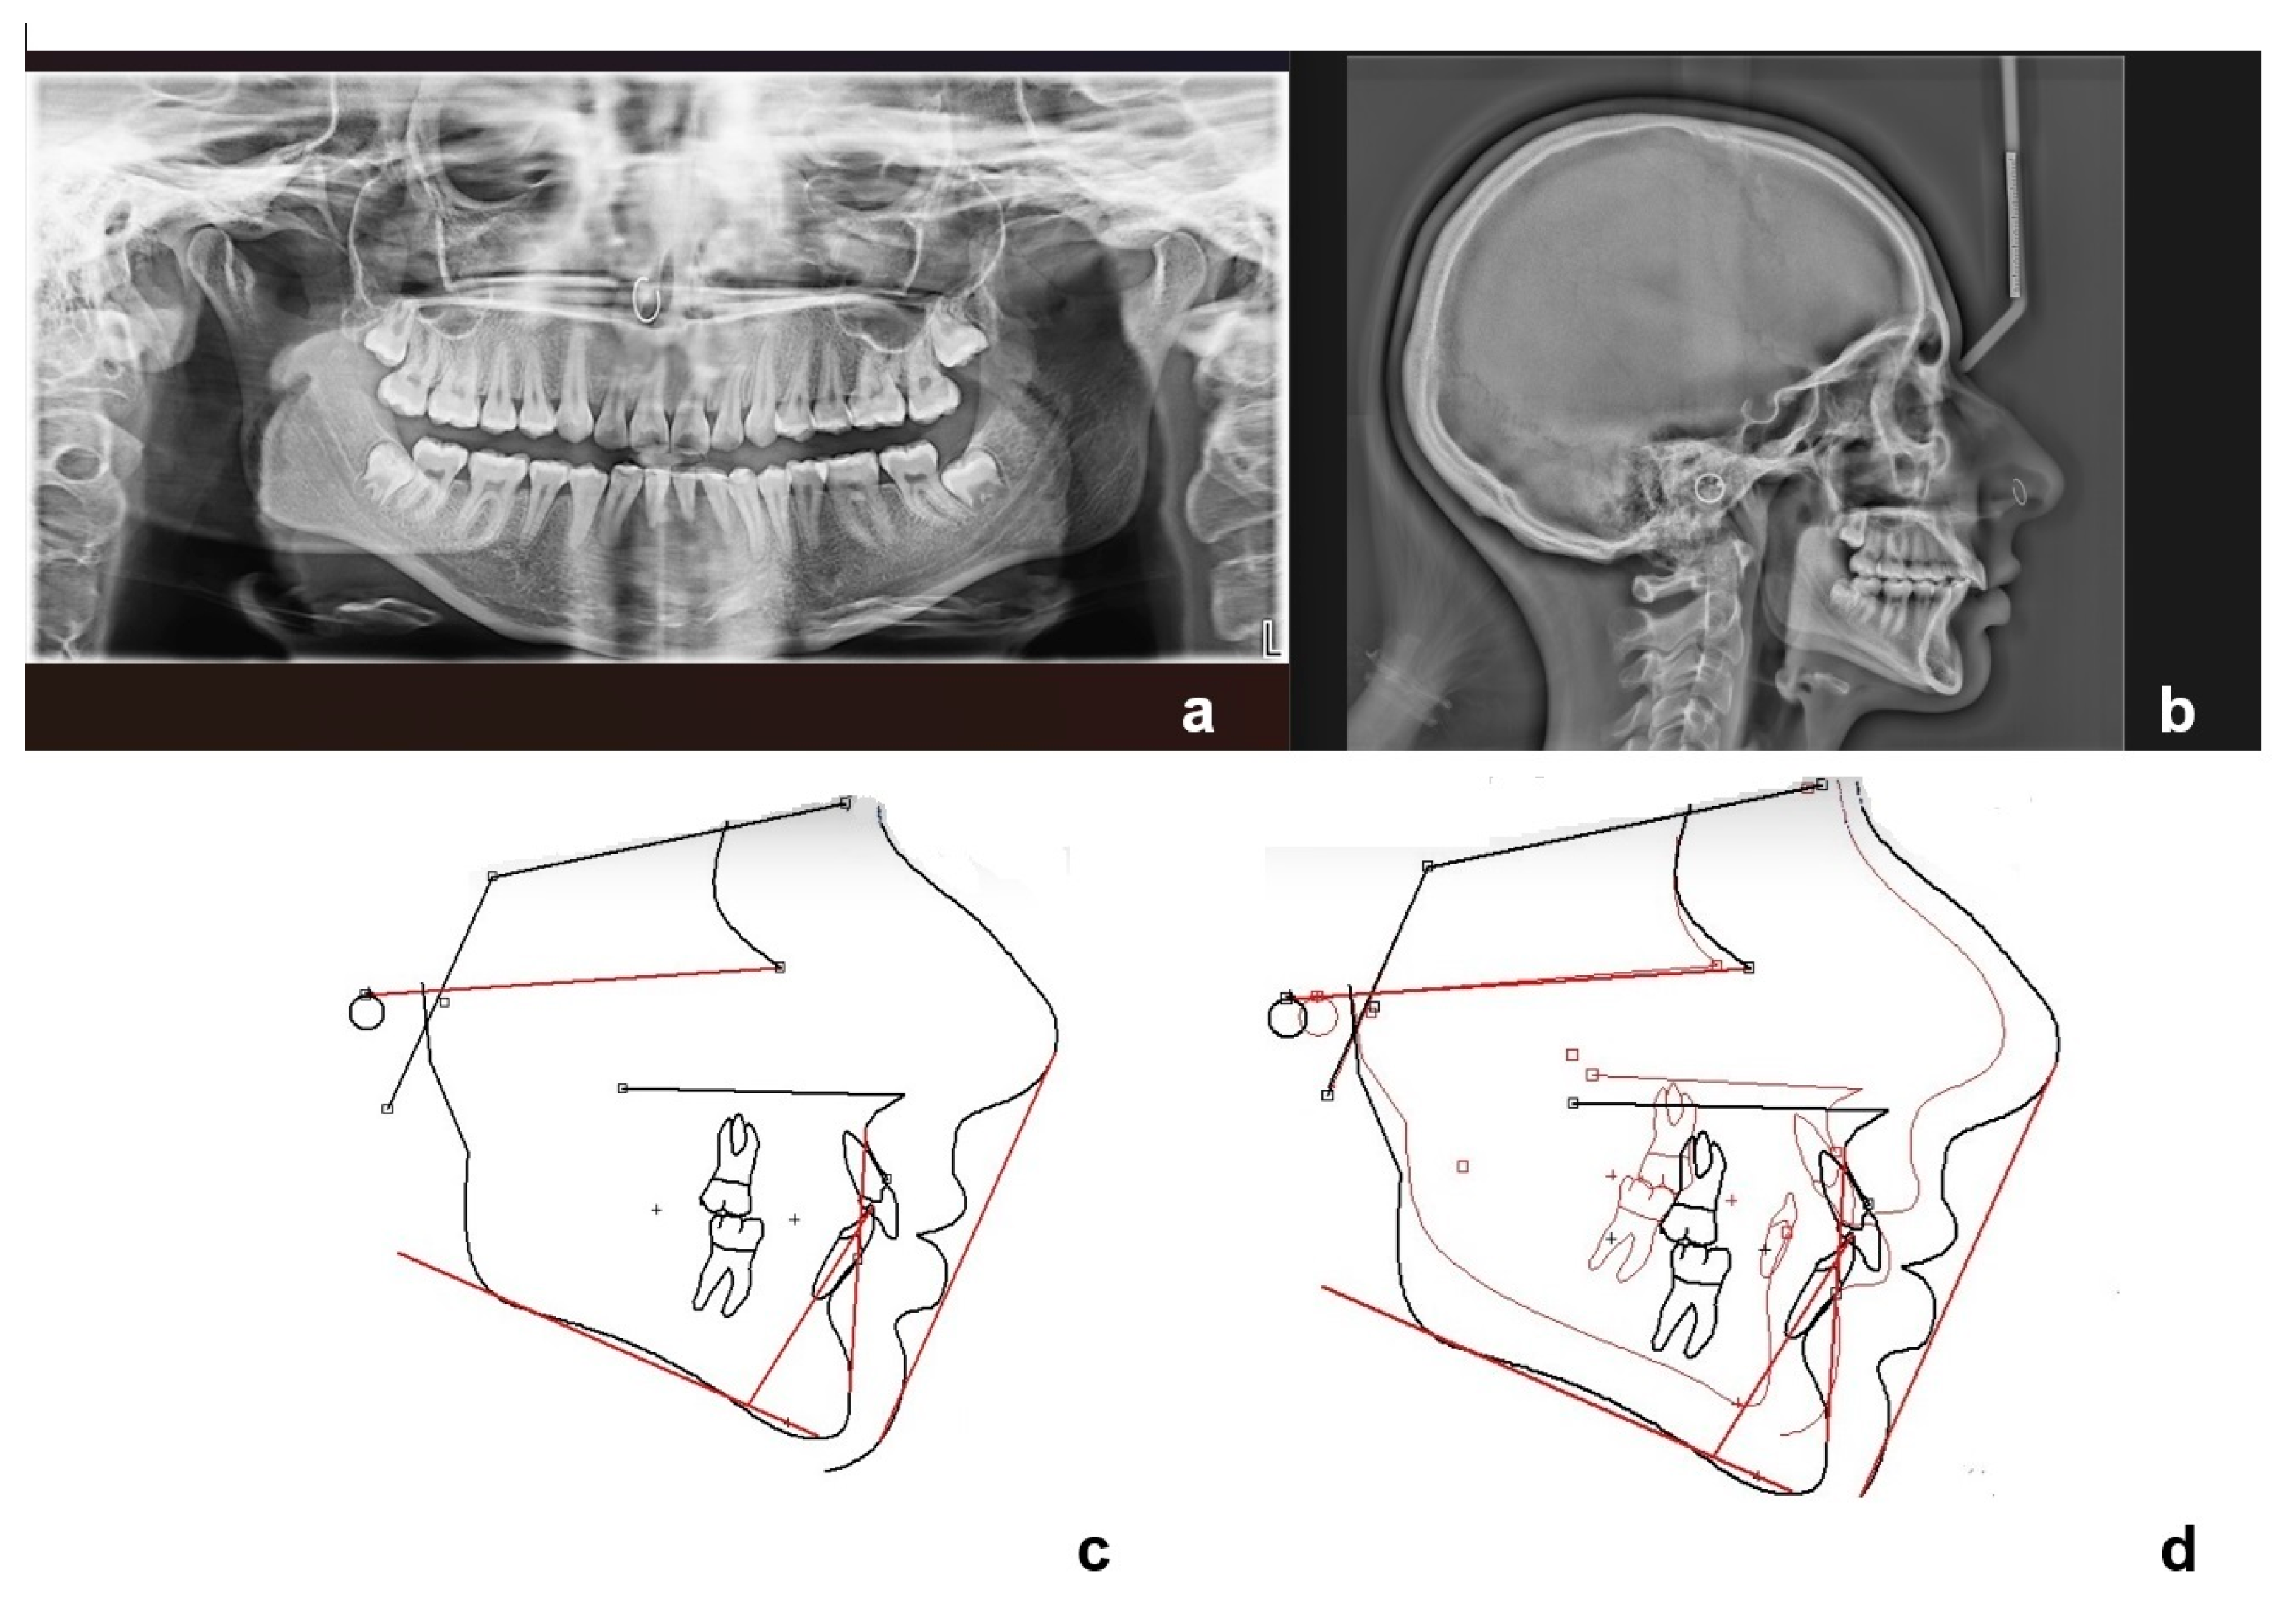

An 11-year-old female patient presented with a Class II molar relationship and a Class II skeletal relationship due to downward and backward rotation of the mandible. Increased overjet (21–71) was recorded, and deciduous lower central incisors and canines were in place while in the upper arch incisors had normally erupted. Upper canines had not been erupted yet and deciduous molars were in place in the lower arch. Radiographic examination with panoramic and lateral cephalometric X-ray in the beginning (Figure 1) revealed that lower central incisors were congenitally missing, and later incisors and canines had their root almost fully formatted. The medical records that were provided indicated that right after birth the newborn was admitted to the neonatal intensive care unit for a cleft of the soft palate and a significant lower jaw retrognathism. Initial cytogenetic report was normal and the check for pathologic findings on chromosome 22, which possibly applies to Di George syndrome (22q11.2 region), was negative. No other local or systemic factors were identified. The cleft was surgically treated at the 15th month of age. The case was characterized as presenting delayed tooth eruption alongside the skeletal and dental Class II relationship.

It was decided to monitor the case for a while with just ordering the extraction of deciduous teeth in order to evaluate the potential of spontaneous eruption of the permanent ones. A progress panoramic X-ray was obtained at that time (Figure 2). Lower deciduous lateral incisors, lower deciduous canines as well as upper and lower first deciduous molars were first extracted.

Figure 1. Initial panoramic (a) and lateral cephalometric X-ray (b) and tracing (c).